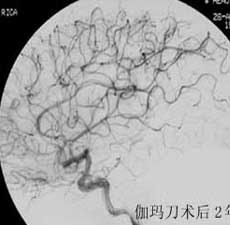

二、脑动静脉畸形(AVM)

---- 血管内栓塞对于单支或少数供血动脉的AVM,特别是新近出血的病例,可以达到微侵袭、痛苦小、疗效迅速的目的。 近来改变栓塞方式,将导管直接放置 畸形血管团内,注射NBCA胶,可使畸形团的解剖 治愈率提高至27%。再加上更细、超 滑的微导管问世,栓塞的并发症更为降低。针对大型、功能区 的AVM栓 塞可缩小其体积,改善血液动力学分布,以利于显 微外科技术切除或放射外科治疗,是后二者的重要辅助手段。

----立体定向放疗(γ-刀、χ-刀)对AVM是一种有希望的选择性治疗方法。据文献报道,AVM治疗后年消失率30%~50%,2年 消失率70%~90%,其消失速度与所用的照射量成正比,与AVM 的大小成反比。从治疗到AVM完全闭合之前每年的出血率 3%~4%,与自然出血史相同,所以对有出血史的患者,应优先采用栓塞或手术方法。大型AVM经若干次栓塞后体积缩小即可 放射治疗。但栓塞物质应是NBCA。其它颗粒或丝线栓塞,均有复发之虞。栓塞加立体定向放疗可使60%~80%的患者免于开颅 手术而获治愈。